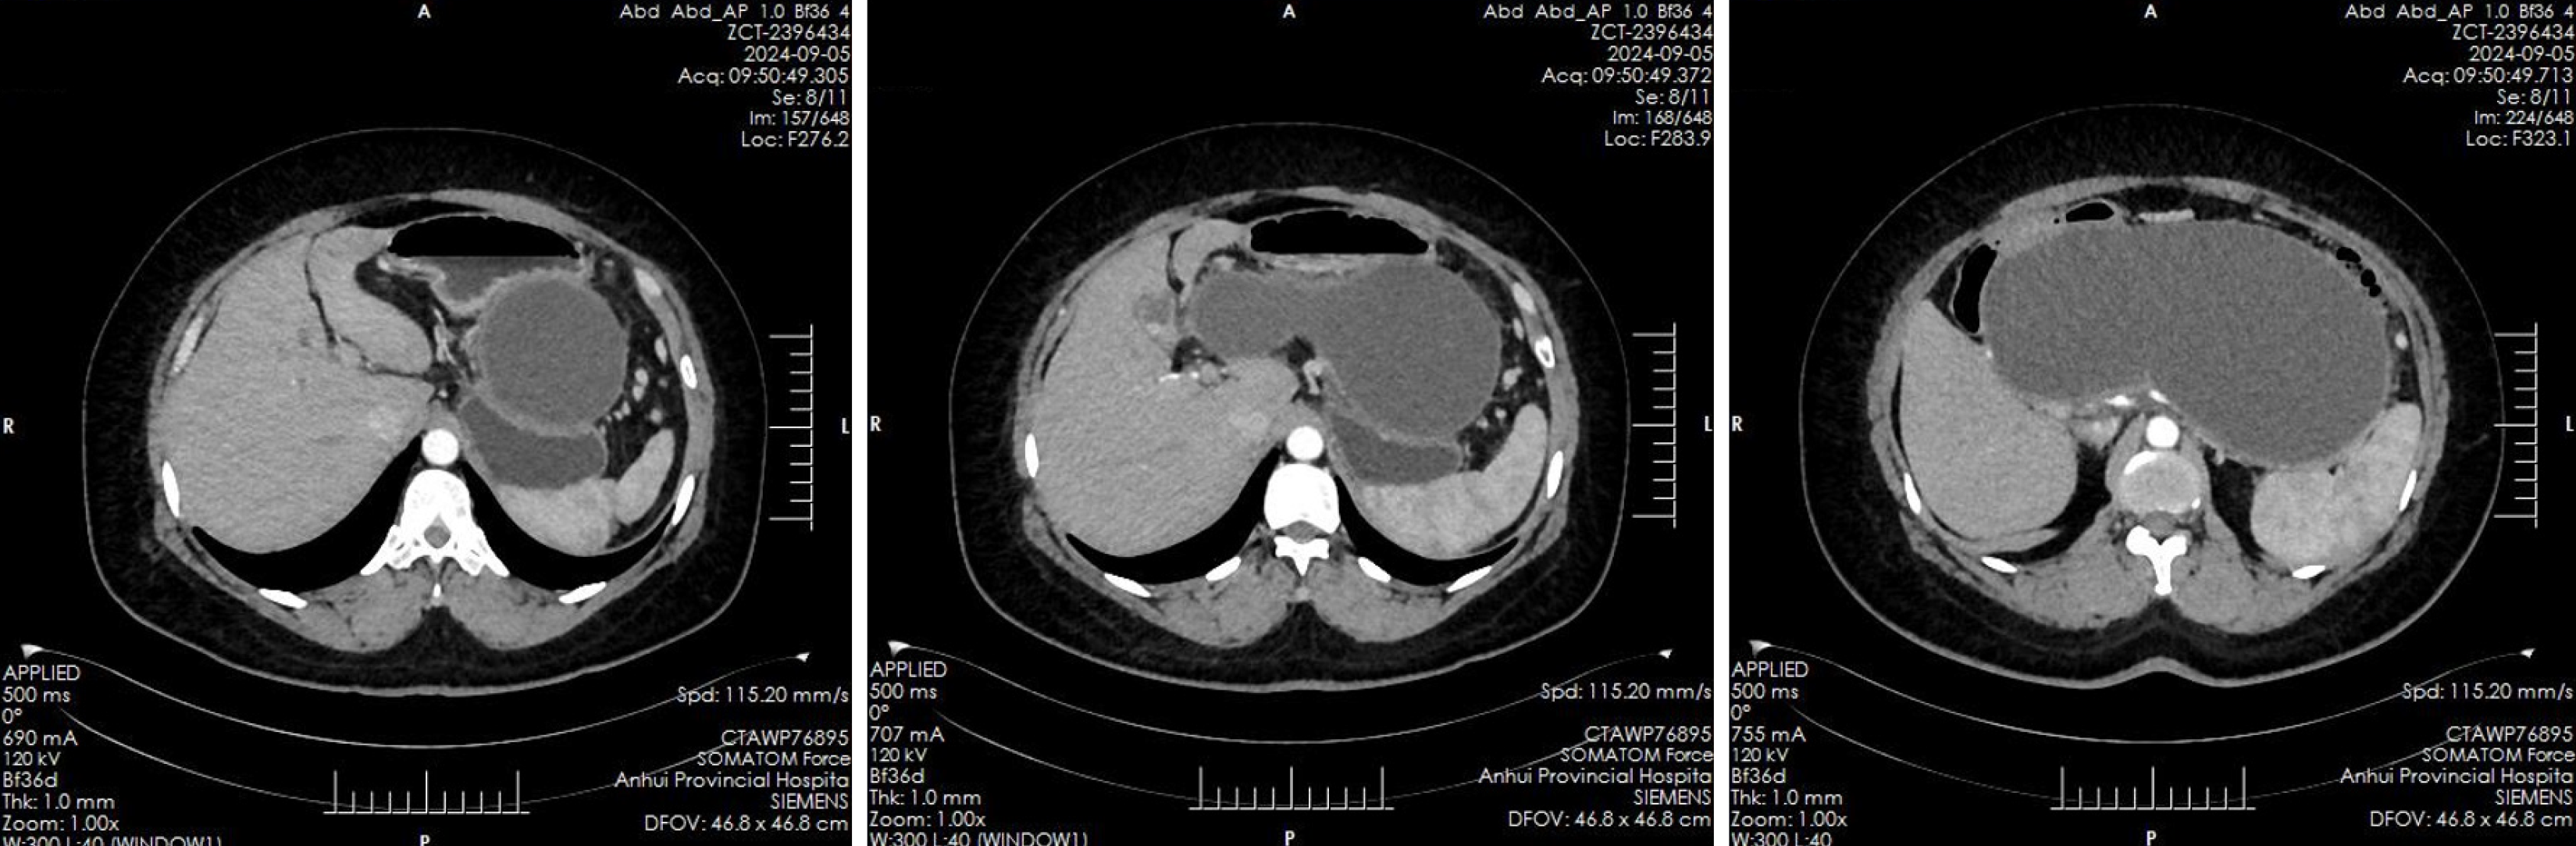

Abdominal ultrasound revealed multiple echogenic clusters with acoustic shadows in the gallbladder, the largest measuring approximately 12 mm × 8 mm. The pancreas exhibited clear, non-echogenic changes, measuring approximately 231 mm × 135 mm × 109 mm. Auxiliary examinations included an enhanced CT scan of the upper abdomen, which revealed an irregular, elliptical cystic low-density shadow approximately 232 mm × 114 mm in size, located in the pancreatic region, with no significant dilation of the intrahepatic or extrahepatic bile ducts (Figure 1). Additionally, multiple gallstones were identified in the gallbladder. Magnetic resonance imaging findings confirmed the presence of a pancreatic cyst and gallstones.

The patient’s history of recurrent pancreatitis and gallstones led to a diagnosis of biliary pancreatitis, with surgical intervention planned for gallstone removal. However, due to the presence of a large pancreatic cyst and associated surgical risks, it was recommended that the cyst be addressed first through pseudocyst drainage. Following multidisciplinary discussions and informed consent from the patient, endoscopic treatment was performed under ultrasound guidance to facilitate the drainage of the PPC.